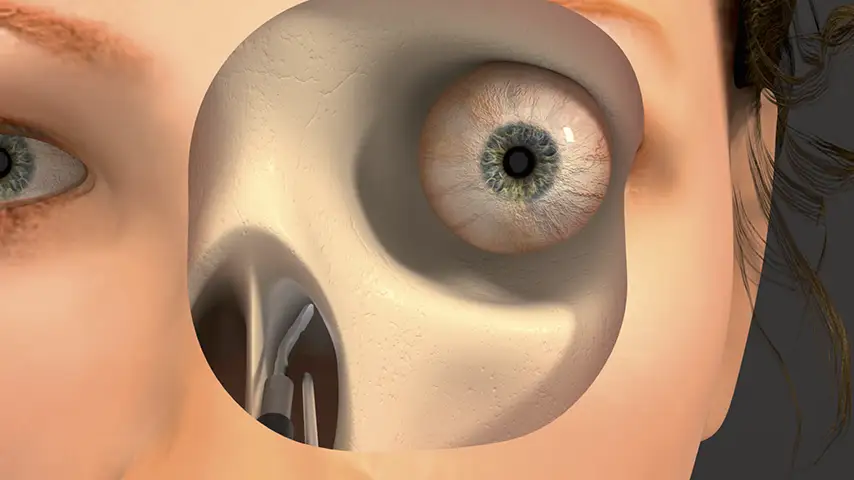

in Orbital Surgery

Osteotomies of orbital bones

Details

Minimized risk of CSF leaks and orbital damage. Improved aesthetics, preservation of fixation materials, and avoidance of substitutes through precise cutting. Reduced heat enhances ossification with implants.

Orbital

decompression

Optic nerve decompression

Details